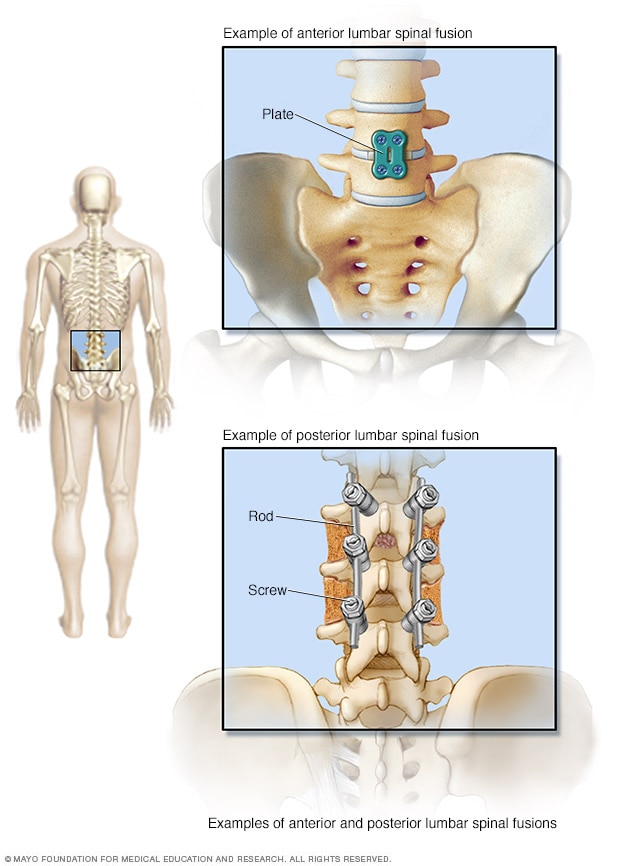

Spinal fusion Mayo Clinic